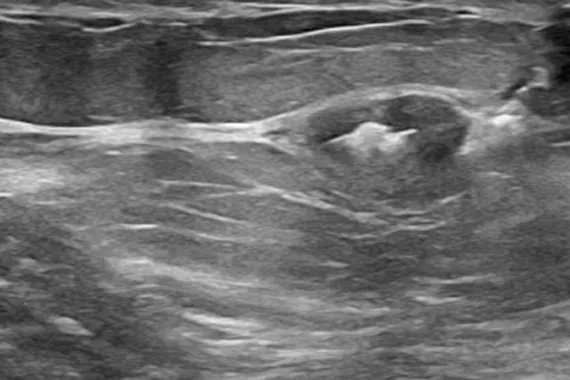

Designed to minimise movement,2 this marker is highly visible in ultrasound upon deployment and still highly visible at 6 weeks post-biopsy, crucial in case of future breast interventions.3 The marker consists of two pieces, a permanent marker and a bioabsorbable suture-like netting.

say ultrasound visibility was good to excellent upon deployment1

Image Gallery